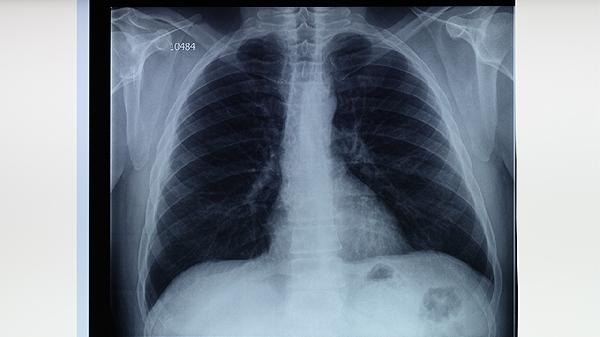

无论是原发性还是继发性肺结核,早期诊断和治疗至关重要。若出现持续咳嗽、发热、体重下降等症状,应及时就医并进行胸部影像学检查和痰液结核菌检测。治疗期间需严格遵医嘱服药,避免自行停药或减量,以免导致耐药性结核病的发生。同时,患者应避免与他人密切接触,防止结核菌传播。通过规范治疗和科学管理,大多数肺结核患者可以完全康复。